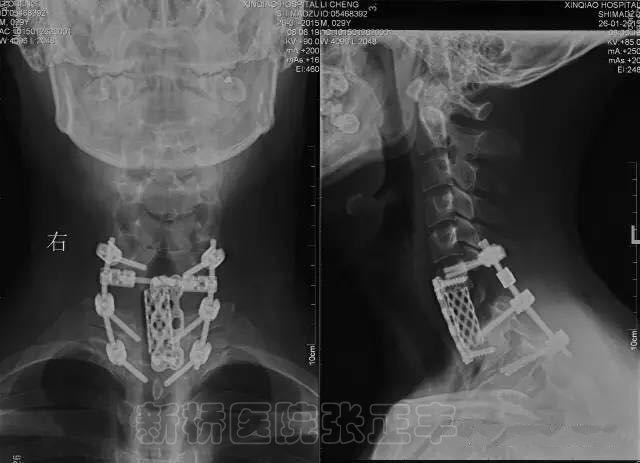

因此,TES手术其实是脊柱肿瘤的两块切除,而非真正意义的整块切除。在颈1到颈6椎除了要保护脊髓,还要保护椎动脉,在分离和游离椎动脉时,需要分多块切除横突孔,所以颈椎肿瘤最多能做到分块切除,而不能做到真正意义的TES手术。目前颈7到腰5椎能做到两块切除的TES, 在颈1到颈6椎有人提出矢状位的TES手术,想想这个概念总觉得有别扭的地方。

2008年开始颈1和颈2椎弓根徒手置钉,2009年开始下颈椎椎弓根徒手置钉,上下颈椎置钉数目没有统计,但肯定分别超过百枚,没有出现过椎动脉损伤。2010年开始在脊柱肿瘤和个别创伤病人主动暴露椎动脉,由于病例稀缺,到目前仅有10余例,非常幸运没有出现过损伤。

椎动脉显露